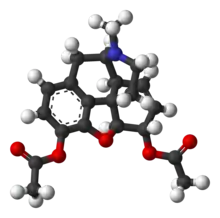

Propiedades físicas y químicas

Síntesis

Se obtiene mediante un proceso de acetilación de la morfina[53]

La materia prima para uso industrial o de laboratorio durante la síntesis de la heroína es la morfina. La acetilación con anhídrido acético o cloruro de acetilo se produce durante el calentamiento. No es necesario un exceso de cloruro de acetilo, ya que en este caso, el resultado, cloruro de hidrógeno, se une a la parte básica de nitrógeno núcleo morfinanovogo, y parcialmente retirado de la mezcla de gas que desplaza el equilibrio casi por completo hacia la formación de derivados diacetilados. El crudo de la acetilación se purifica por adición de carbón activo y filtrado para ser posteriormente recristalizado en etanol.